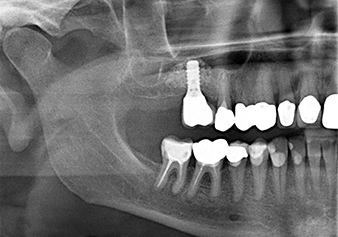

A 49-year-old female patient, a non-smoker and with nothing remarkable in her general medical history, was referred to our oral surgery practice for surgical extraction of tooth 16 and subsequent implantation. After the extraction, the patient experienced mild sinusitis trouble with the resultthat we initially waited six months before carrying out the measure. The residual bone height at the planned implant position measured 3-4 mm (Fig. 1 and 2).